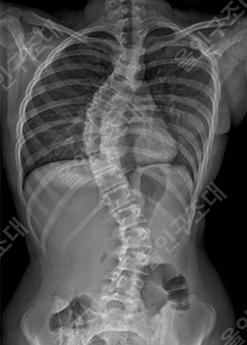

엑스레이에 발기된것도 나오나요?

골반 엑스레이 찍는데

엑스레이에 발기된것도 나오나요?? 하.....